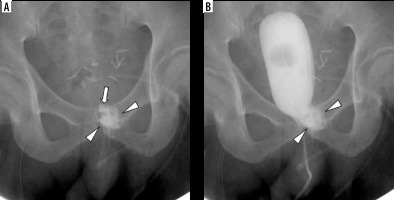

A 59-year-old male with rectal cancer invading the prostate and urinary bladder underwent low anterior resection and radical retropubic proctectomy 15 months ago. One month later, the patient presented with persistent urinary leakage at the posterior aspect of the vesicourethral anastomotic site, which was confirmed by cystography (Figure 1). The amount of urinary leakage through the JP drainage tube was 350 ml/day, and its nature was urine. Although the indwelling Foley catheter was retained for 1 month, the fistula persisted without infection.

Cystography (A) and axial computed tomography scan (B) 1 month after prostatectomy. Contrast agent leakage (arrows) is shown at the posterior aspect of the vesicourethral anastomotic site on the left side